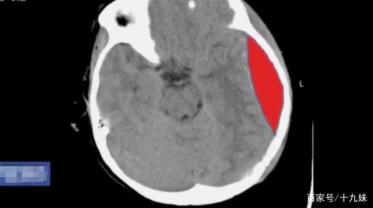

结果很快出来了,医生一看不得了,这个6岁的小女孩竟然出现了脑出血,长度约2cm,出血量约20ml,更为致命的是,小孩的颅骨还有两处裂痕。事不宜迟,医院赶紧联系医生和专家进行了会诊。

这种情况下,一般要进行开颅手术把淤血清理掉,而鉴于孩子年纪小,术中很容易出现低血压,另外稍不注意就会损伤到脑神经,这都是十分危险的。但如果不做手术的话,从孩子反应迟钝的表现来看,现在血液已经压迫到了脑神经。如果有继续出血的情况,那就很可能导致瘫痪、语言丧失,甚至危及生命。讨论的最后结果,医生觉得做开颅手术很有必要。